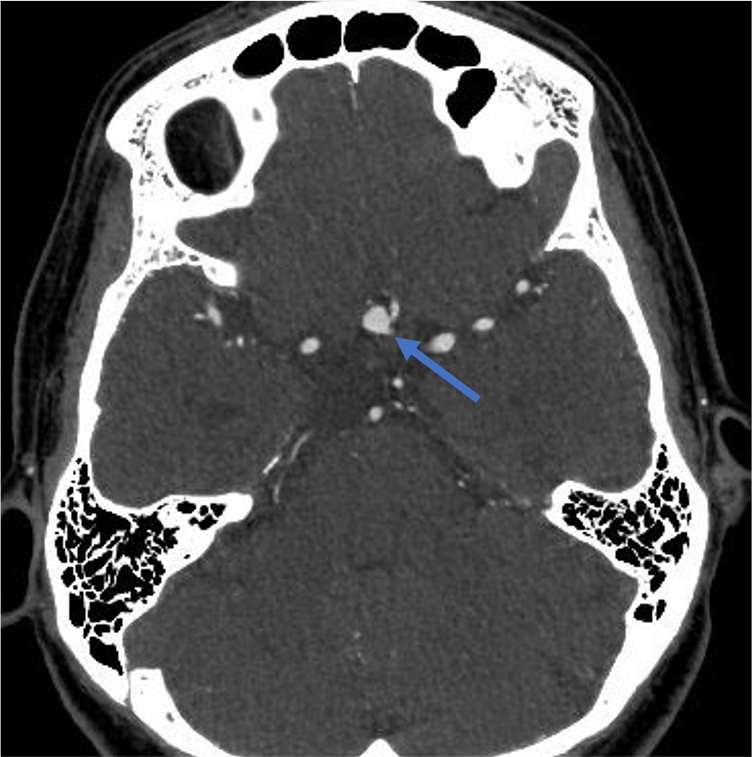

頭部CTAでのブレブを伴った前交通動脈瘤の1例

症例は60代女性。めまいを主訴に近医脳神経外科を受診した。高血圧を認めたほか頭部MRIで前交通動脈瘤を指摘され、精査・加療目的で当院脳神経外科を紹介受診した。頭部CTAでは前交通動脈にブレブを伴う6mm大の嚢状動脈瘤を認めた。検討会、本人との相談にて、クリッピング術の方針となった。検査2ヶ月後に開頭クリッピング術が施行され、合併症なく退院した。その後、再発なく経過している。

動脈瘤の形状に関しては、不整な膨らみ(ブレブ)がある場合、破裂リスクが約1.6倍高まることが知られています。ただし、ブレブは小さな突出として認められることもあるため、詳細な評価には高い空間分解能を有するCTAが有用です。

提示症例は、ブレブを有する前交通動脈瘤のケースですが、CTA・MRAの両方で動脈瘤の不整な形態は視認可能です。ただし、CTAの方がより詳細にブレブを描出できていることがわかります。

CT技術や撮像プロトコル設定について

使用したCT装置Aquilion Precisionは、検出器サイズが0.25mmかつX線の焦点が極小焦点であり、血管や骨構造などの微細な構造を明瞭に描出できる高精細CT装置である。一方で、検出器が高精細であるがゆえにX線の検出効率が低く、画像ノイズが発生しやすいという課題もある。これに対し、Deep Learningを用いたノイズ除去再構成技術であるAiCEを併用することで、ノイズを抑えながら、穿通枝レベルの細血管や動脈瘤の形態を明瞭に描出することが可能となっている。そのため、脳神経外科医師からは本装置を指定した検査依頼が非常に多く寄せられている。